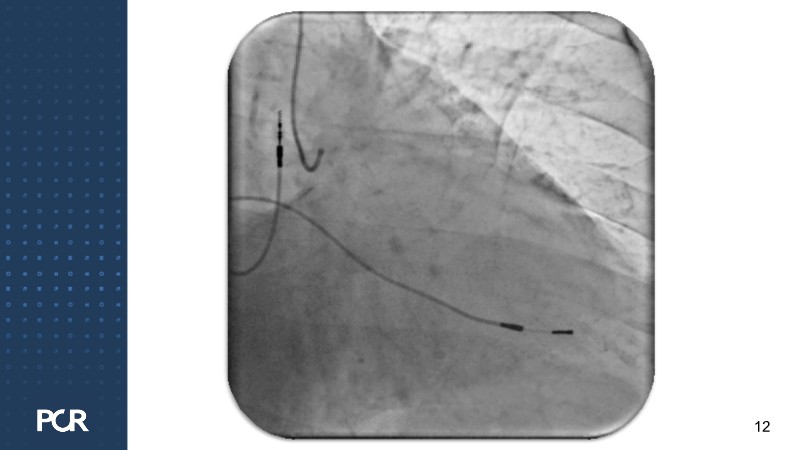

This session offers a comprehensive overview of the management of high bleeding risk (HBR) patients with multivessel disease. Through expert discussion and a live case demonstration featuring a complex elderly patient, it highlights how intracoronary imaging and physiology can guide procedural decisions and improve outcomes in this vulnerable population. The session also explores PCI strategies adapted to bleeding risk profiles, with a particular focus on the live case approach, including the use of sirolimus-eluting stents to optimise both procedural safety and long-term results.